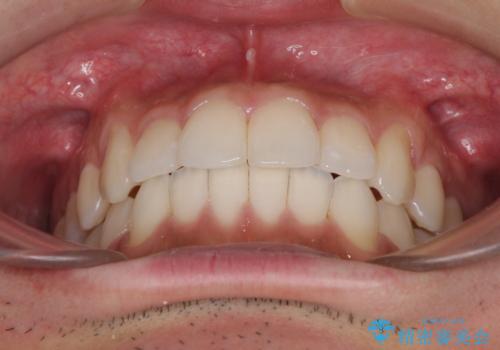

前歯のデコボコを治したい インビザライン矯正治療

- 前歯のデコボコを治したいとのことで来院された患者様です。

上下顎ともに歯列全体の後方移動とIPR(歯と歯の間を削る)によってデコボコが解消するように設計し、インビザラインにより治療を行うこととしました。

毎日22時間以上しっかりとマウスピースを装着していただいたので、スムーズに治療が進みました。歯と歯の間を削ることでうまくスペースコントロールでき、1年強で終えることができました。